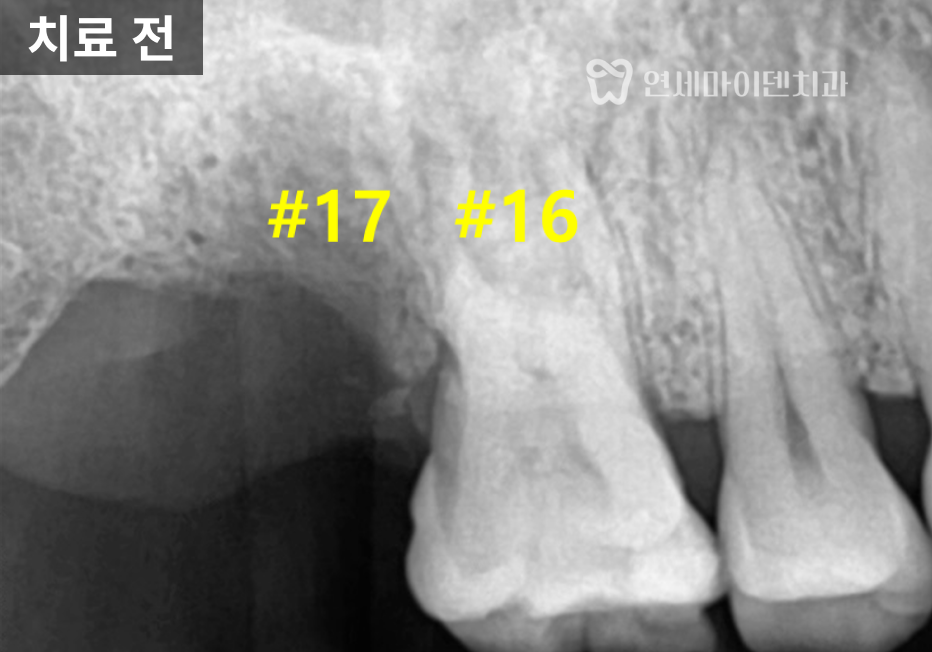

검사 결과,

17번 치아는 뼈 높이가 전반적으로 낮았고

상악동 점막이 두꺼워진 상태였습니다.반면 16번 치아는

깨지고 염증이 있었지만

정밀 평가 결과

발치된 17번 어금니 부위는

뼈의 높이가 전반적으로 낮아져 있었습니다.CT 분석 결과,

상악동 바닥이 아래로 내려와 있었고

점막도 다소 두꺼워진 상태였습니다.이러한 상황에서

임플란트를 단순 식립할 경우

상악동 내부를 침범할 위험이 있어

상악동 거상술을 동반한 임플란트 식립이

필요했습니다.